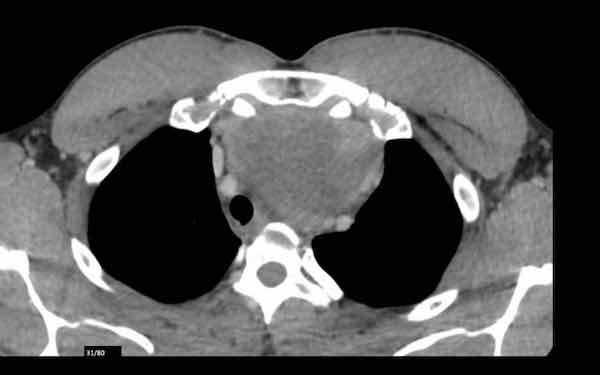

Đây là hình ảnh của một nam giới 24 tuổi.

Hãy quan sát kỹ các hình ảnh trước.

Câu hỏi: đây có phải là tuyến ức bình thường không?

Hình ảnh

Mặc dù tuyến ức này khá lớn, nhưng có hình tam giác bình thường và chứa mỡ (mũi tên).

Đây là tuyến ức bình thường.